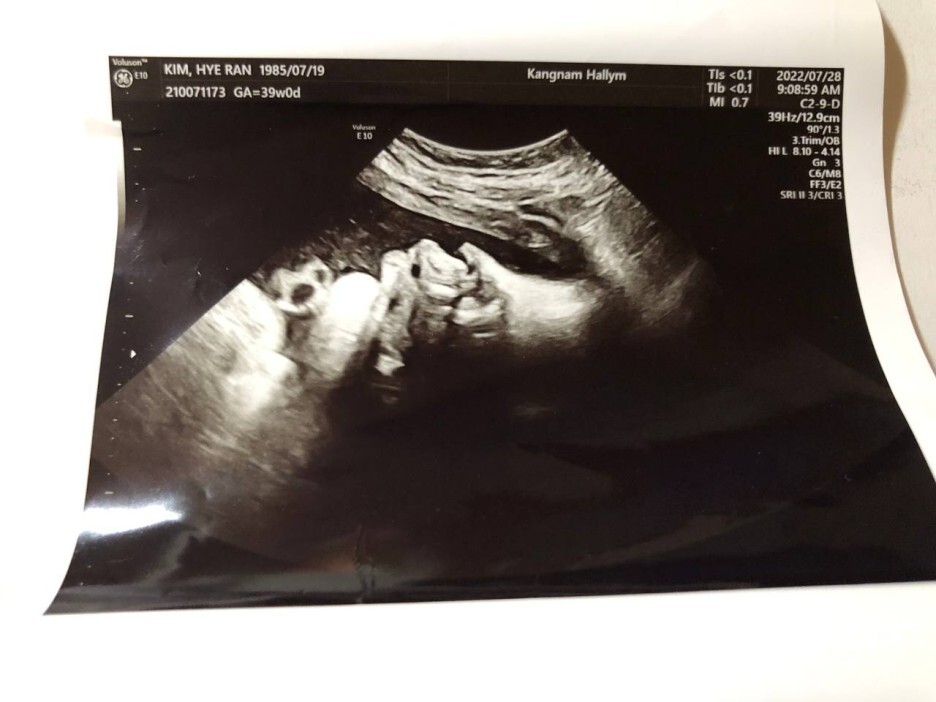

7월 28일 목요일(39주 차 0일)

BPD(Biparietal Diameter, 위에서 볼 때 태아 머리 단면의 가장 긴 길이): 9.57cm

HC(Head Circumference, 태아 머리둘레): 34.17cm

AC(Abdominal Circumference, 배 둘레): 36.58cm

EDD(Expected Date of Delivery, 출산 예정일): 2022년 8월 4일

FL(Femur Length, 허벅지뼈 길이): 7.21cm

GA(Gestational Age, 임신 주차): 39주 차 0일

EFW(Estimated Fatal Weight, 태아 예상 체중)=EBW(Estimated Body Weight): 3850g

FHR(Fetal Heart Rate, 심장박동 수): 135bpm

CL(Cervical Length, 자궁경부 길이): 정상

AF(Amniotic Fluid, 양수): 정상